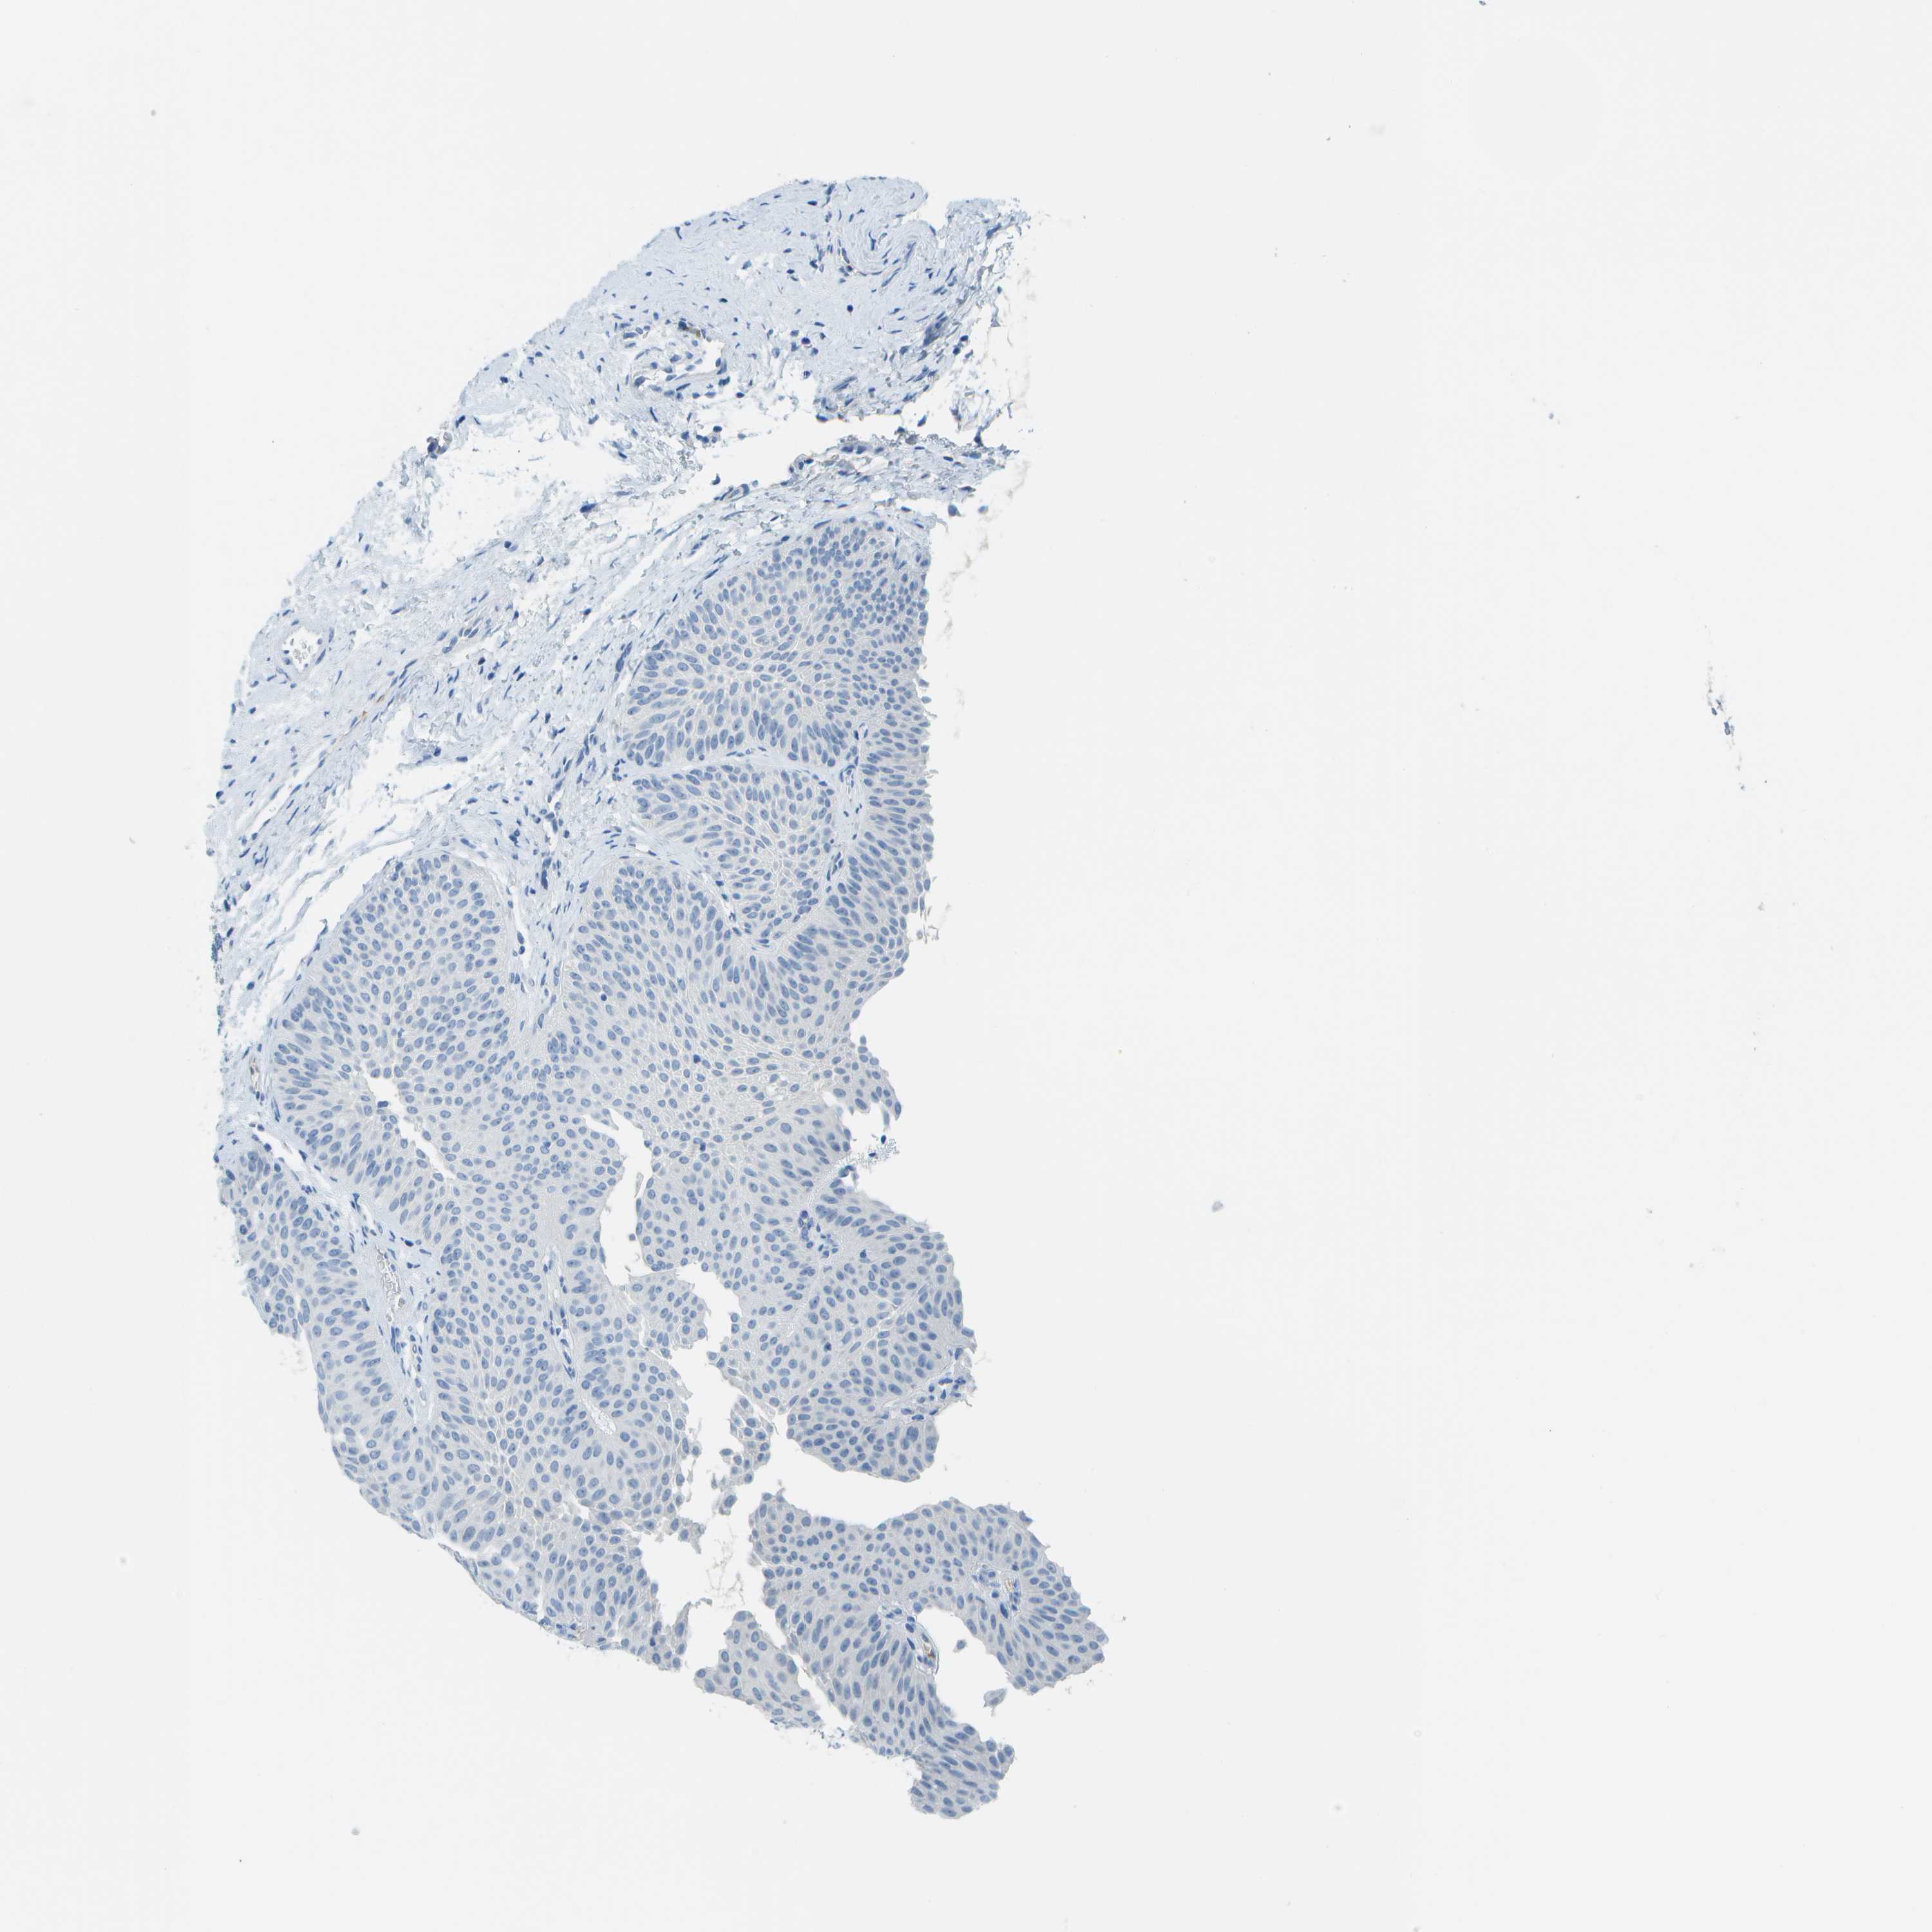

UROTHELIAL CANCER - Protein expressioni

A mouse-over function shows sample information and annotation data. Click on an image to view it in a full screen mode. Samples can be filtered based on level of antibody staining by selecting one or several of the following categories: high, medium, low and not detected. The assay and annotation is described here.

Antibody stainingi

Antibody staining in the annotated cell types in the current human tissue is reported as not detected, low, medium, or high, based on conventional immunohistochemistry profiling in selected tissues. This score is based on the combination of the staining intensity and fraction of stained cells.

Each image is clickable and will lead to virtual microscopy that enables deeper exploration of all samples and also displays staining intensity scores, fraction scores and subcellular localization as well as patient and tissue information for each sample.

Antibody HPA018852

Antibody CAB016722

Urothelial carcinoma, Low grade

Urothelial carcinoma, High grade